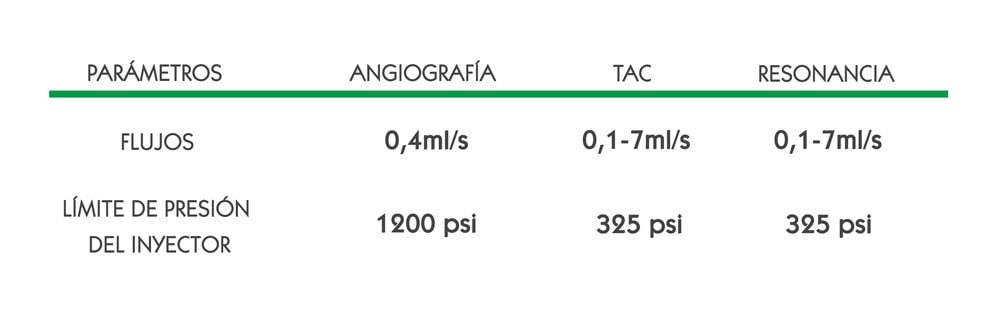

Sin embargo, los catéteres CT rated no son solo compatibles con las inyecciones de alta presión en TAC ya que otras pruebas diagnósticas usan la alta presión: la resonancia y la angiografía.

La alta presión se necesita en los casos que requieren inyectar un producto de contraste.

Este producto de contraste se inyecta con alta presión: es necesario poder administrarlo a gran velocidad. Mediante un inyector que genera una presión muy alta se consigue entonces un alto flujo. El alto flujo del contraste al salir del inyector no es el mismo al entrar en la vena: se ve reducido por el prolongador que conecta el inyector al acceso vascular y la longitud del catéter.

La presión y el flujo son entonces interdependientes.

Entonces, respecto al flujo, ¿de qué velocidad estamos hablando?

Para poder conseguir las imágenes adecuadas se requiere, en adultos, flujos de entre 3 y 7ml/s, según el órgano que se quiera explorar. Los flujos que alcanzar dependen también del tipo de paciente (niño o adulto):